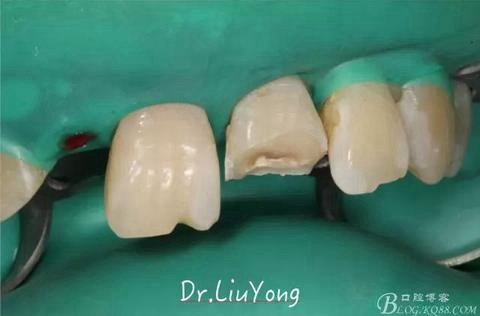

手術(shù)后1月,決定先行臨時(shí)修復(fù),由于患者為重度深覆合,因此考慮將上前牙通過(guò)臨時(shí)修復(fù)體,降低切端的高度,減輕覆合,同時(shí)將舌傾的牙冠形態(tài)調(diào)整為較為直立。B2為根折到齦下1.5mm,考慮到患者無(wú)法接受正畸,同時(shí)如果近中鄰面行冠延長(zhǎng)手術(shù)會(huì)帶來(lái)后續(xù)的黑三角美觀問(wèn)題,因此選擇在橡皮障下行齦壁提升,然后A2纖維樁+樹脂核,A1-B2臨時(shí)樹脂貼面修復(fù),A2臨時(shí)冠修復(fù)。

由于上前牙外傷后未及時(shí)行松牙固定,已拖延1月,因此先行松牙固定,嘗試保留。因A2冠根折,牙冠缺失,故行A1-B3松牙固定,選擇鄰面樹脂粘結(jié)固定,因?yàn)檠例l極易出血,因此選擇橡皮障下用流體樹脂進(jìn)行松牙固定。同時(shí)A2B1根管治療。